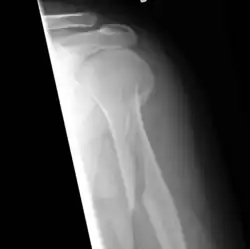

Spiral fracture

A spiral fracture (a.k.a. torsion fracture) is a bone fracture occurring when torque (a rotating force) is applied along the axis of a bone.[1] Spiral fractures often occur when the body is in motion while one extremity is planted. For example, a spiral fracture of the tibia (the shinbone) can occur in young children when they fall short on an extended leg while jumping. This occurrence is known as "toddler's fracture". Spiral fractures are also recognized as being suspicious in very young children since to obtain a fracture of this sort requires forceful twisting or jerking of the limbs. Child abuse (physical abuse) and certain conditions such as osteogenesis imperfecta (OI) are considered differentials when identifying spiral or torsion fractures.[2]